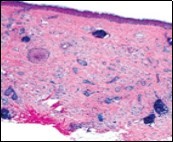

Lesions are generally superficial and infrequently invade lower dermis. Tendency for peri-neural or intra-neural infiltration, cogitated in adjunctive cutaneous carcinomas, is exceptional in desmoplastic trichoepithelioma. Nevertheless, desmoplastic trichoepithelioma can be exemplified as a component of particularly desmoplastic, cutaneous carcinomas demonstrating foci of peri-neural involvement 4, 5. Figure 1, Figure 2, Figure 3, Figure 4, Figure 5, Figure 6, Figure 7, Figure 8.

Figure 1.Desmoplastic trichoepithelioma demonstrating aggregates of basaloid cells with numerous keratinous horn cysts interspersed in an intensely fibrotic stroma 9.